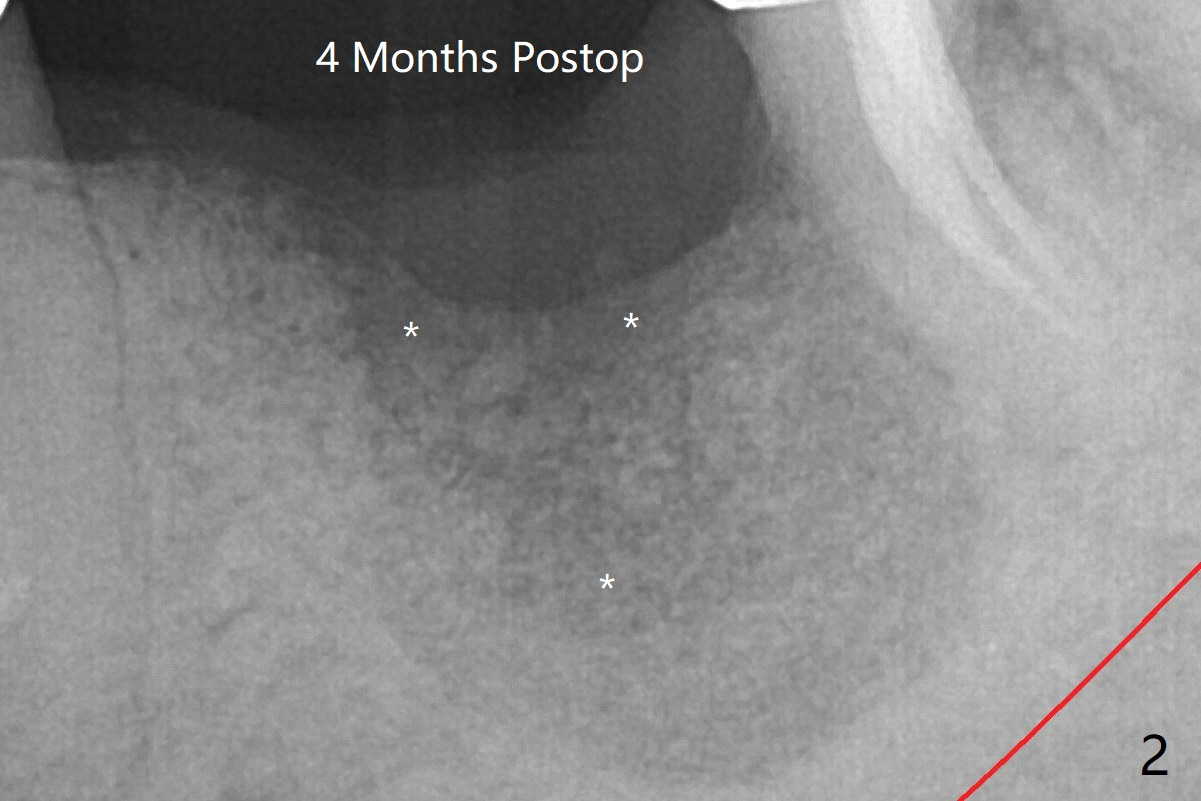

The low density bone in the middle of the socket is ignored (Fig.2 *, 3 S (soft)).  植骨后四个月,磨刀霍霍。Steven: 可能不够尤其远中,可能要再植骨,植入后没有初始稳定也不行。

姜老的辣。如果是你,第一次植骨,四个月前,该怎么做的更好?如果现在再植骨,你的计划?

Steven: Sticky 骨的经验不多,可能之前prf膜有软组织长入,也可能之前没刮干净,病人有其他系统疾病。一般我尽量over graft+膜(可吸收或不吸收的)+一期减张缝合。Slow down and be generous on graft material

病人来时,我也没有注意到植骨当中骨质密度低下,星号,它有可能当中血供不足导致。总之,没把它当一回事,应该再植骨。匆忙开始植牙